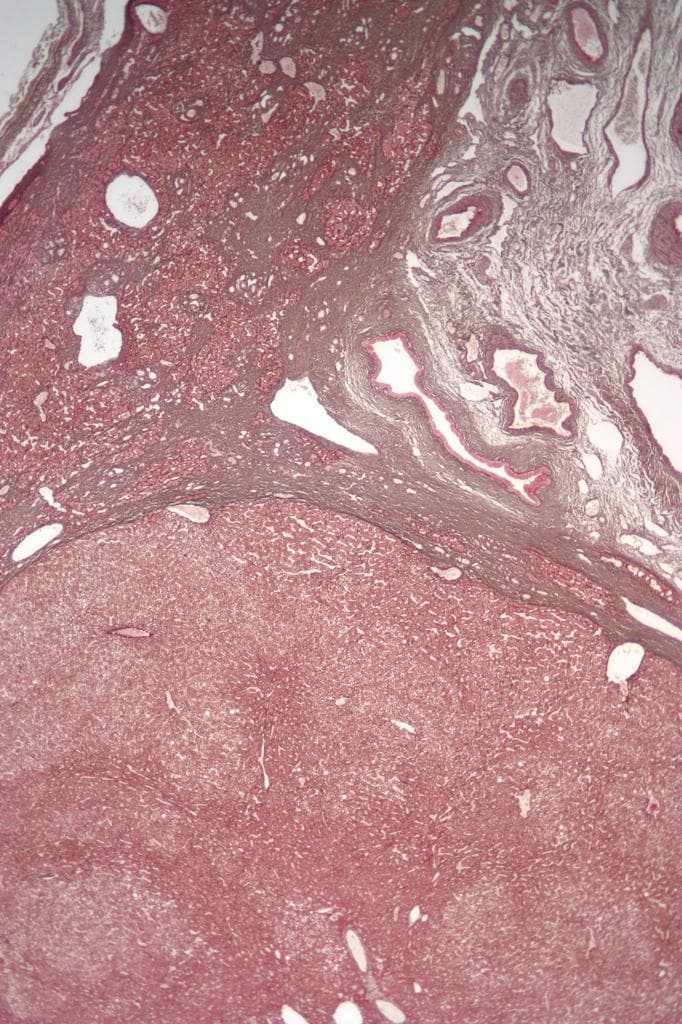

Hình ảnh điển hình của tăng sản khu trú dạng nốt (focal nodular hyperplasia), là một trong số ít các tổn thương có khả năng tích tụ mạnh thuốc cản quang đặc hiệu tế bào gan.

- "Tăng sản khu trú dạng nốt (FNH) thường cho thấy tăng cường mạnh ở thì động mạch, kèm sẹo trung tâm và bắt thuốc đồng đều ở thì cửa và thì muộn."

- "Trên hình ảnh thì gan-mật với Primovist, FNH thường giữ thuốc cản quang do sự hiện diện của tế bào gan hoạt động, giúp phân biệt với ung thư tế bào gan dạng tuyến."